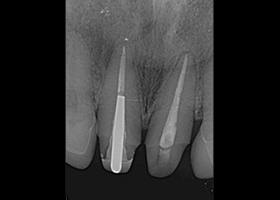

1.術前口內正面照、局部X光片。

proimages/case/cosmetic/pic_case-020.jpg

proimages/case/cosmetic/pic_case-021.jpg